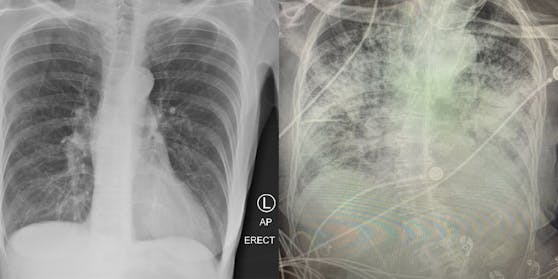

Die Spätfolgen des Coronavirus auf den menschlichen Körper sind noch nicht umfassend erforscht, erste Berichte von Medizinern geben aber Grund zur Sorge. Eine Assistenzprofessorin in Texas, Brittany Bankhead-Kendall, schlägt jetzt Alarm: “Nach einer überstandenen Covid-Erkrankung sehen Lungen schlimmer aus als jede Raucherlunge, die wir je gesehen haben”, so die Ärztin auf Twitter. Wie der Fernsehsender WGN America berichtete, zeigen Röntgenbilder einen dramatischen Unterschied zwischen einer gesunden Lunge, einer Raucherlunge und einer “Post-Covid-Lunge”.

Luft wird auf den Bildern schwarz dargestellt, Knochen und organisches Material weiß. Laut Bankhead-Kendall können Röntgen von Covid-Patienten fast vollständig weiß aussehen, was auf intensive Vernarbung und einen Mangel an Sauerstoff hinweist. Im Vergleich dazu zeigen Raucherlungen auch nach jahrelangem Tabakkonsum noch weniger ausgeprägte Spuren.

Lugnen-Schaden trotz symptomlosen Verlaufs

Besonders heimtückisch: Sogar Corona-Patienten, deren Infektion symptomlos blieb, zeigen teils schwere Lungenschäden. “Es gibt noch immer Leute die sagen ‘Es geht mir gut, ich habe keine Probleme’. Und dann schaust du ihr Lungenröntgen an und es sieht ganz schlecht für sie aus”, so Bankhead-Kendall. “Auch wenn man jetzt keine Probleme hat, kann das Lungenröntgen darauf hindeuten, dass man mit Spätfolgen rechnen muss.”